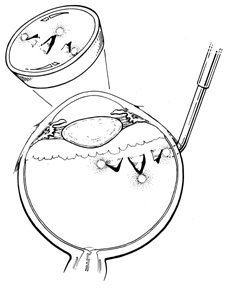

Current cryotherapy instrumentation employs expansion of high-pressure nitrous oxide at the tip of a probe generating temperatures as low as 89°C. The temperature effect is confined to the tip of the probe by an insulating sleeve. A probe 2.0 to 2.5 mm in diameter usually is used for retinal work. Treatment of retinal breaks and pathologic conditions requires accurate placement of the cryoprobe tip. The surgeon must be certain that the indentation visualized with the indirect ophthalmoscope is the tip of the probe and not the shaft. Confusion between the tip and the shaft of the cryo-probe can cause inadvertent posterior freezes.33 To minimize the possibility of this complication, the surgeon must indent only with the tip of the cryoprobe (Fig. 10). It is also helpful to perform the first freezes at the most anterior aspect of the area requiring treatment to assess both location and intensity of treatment.

Fig. 10. A. Inadvertent posterior placement of cryoprobe tip caused by visualization of cryoprobe shaft. B. Correct placement of cryoprobe tip.